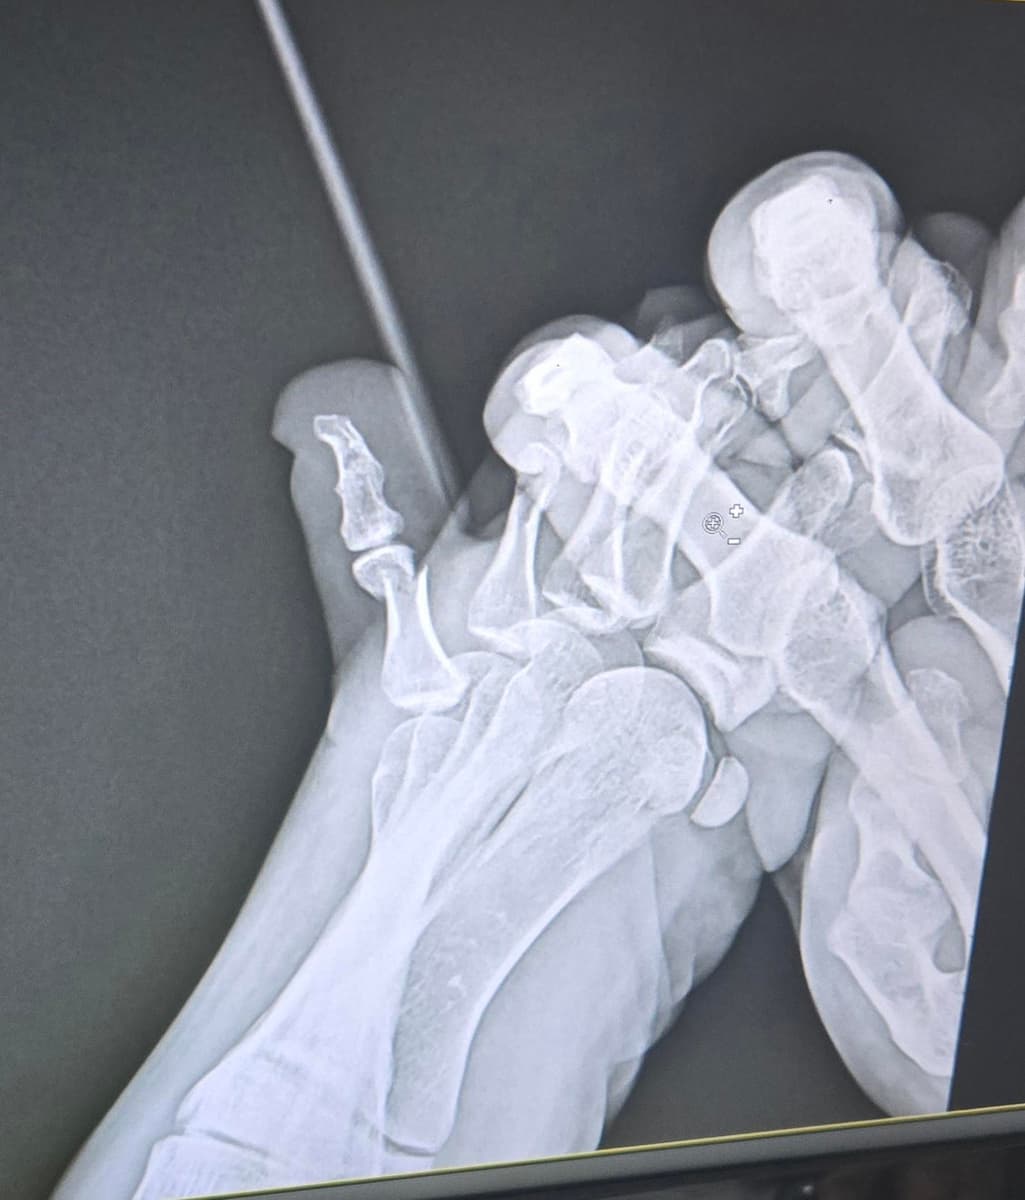

오늘 다른 병원에서 찍은 엑스레이 사진이고 테이핑만 하고 6주 정도는 봐야된다고 하셨어요

Q. 제 상태가 어떤 상태인지 자세히 알고 싶어요. 금 갔다고 하셨는데 측면 사진에서 어긋난 보이는 건 뭔지 특히 궁금합니다!(의사선생님께 자세히 못 여쭈어봐서..ㅜㅜ)

새낄 발가락 골절은 보통 뼈가 크게 벌어지지 않은 금 간 상태라면 수술은 꼭 필요하지 않을 수 있습니다. 또한 엑스레이에서 어긋나 보이는 건 충격으로 미세한 틀어짐인데, 의사 선생님이 수술은 필요 없다고 한 건 기능에 문제 없는 정도라고 판단하신 것 같습니다.

X-ray에서 보이는 어긋난 부분은 골절 부위의 미세한 변위로, 금이 가면서 뼈 조각이 살짝 벌어진 싱태일 수 있습니다.

원래 뼈구조이며, 발가락 뼈의 측면을 촬영한 것으로 보입니다.

우선 현재 사진만으론 엑스레이를 확인 할 수 없지만 측면에서 어긋난것으로 보여집니다.